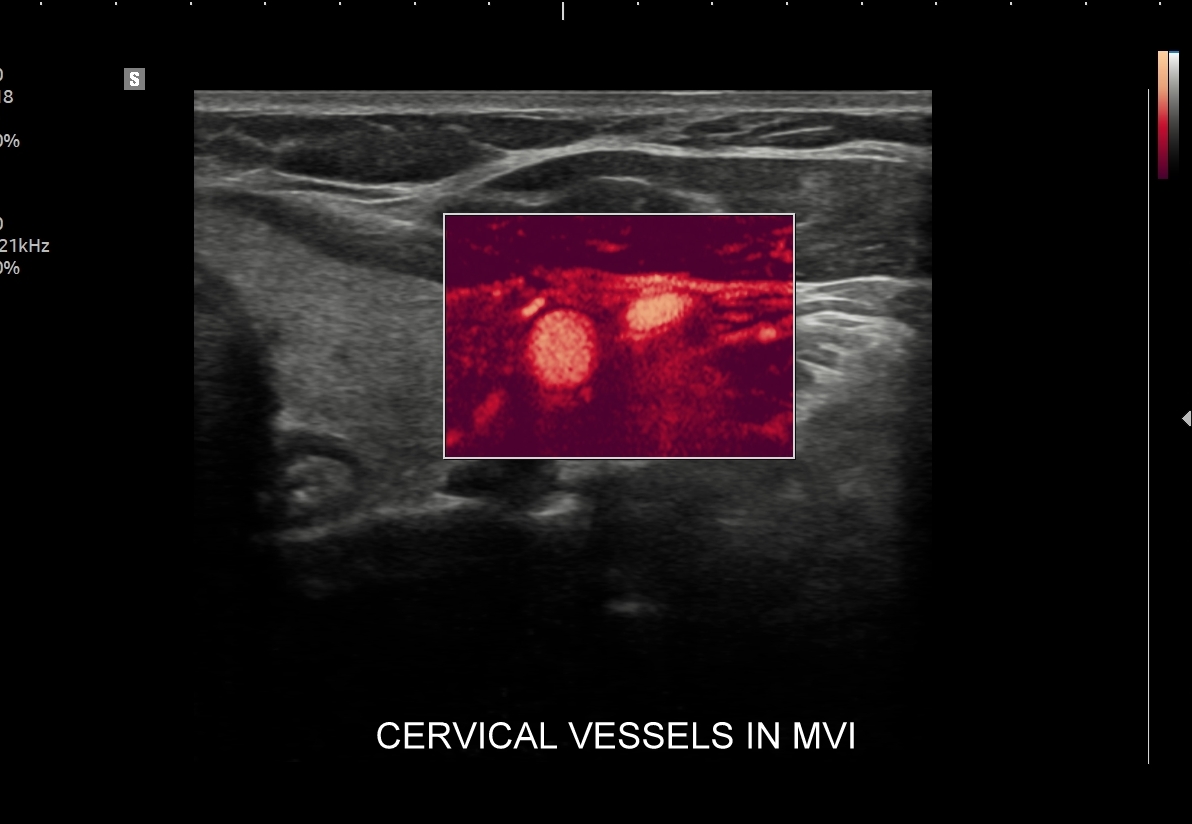

Aktualny kurs USG tarczycy i szyi z naciskiem na zastosowanie obrazowania multiparametrycznego MPUS rozszerzony jest m. in. o użycie trybów mikrounaczynienia MVI, o badania elastograficzne, ocenę funkcjonalną narządów szyi oraz zastosowanie CEUS w diagnostyce zmian ogniskowych szyi. Jest pierwszym w Polsce szkoleniem w tak zaprojektowanej multimodalnej i interdyscyplnarnej konstelacji. Materiał ujęty w kursie obejmuje obszerny materiał zdjęciowy, 13 godzin wykładów oraz ponad 1000 stron prezentacji !

Multiparametryczne badanie USG (MPUS) jest rozwinięciem klasycznego USG tarczycy i szyi pod postacią jednoczasowego zastosowania różnorodnych technologicznie trybów obrazowania USG, zarówno tzw. „nowych”, jak i „starych”. Wśród nowych najważniejszym jest obrazowanie mikrounaczynienia (MVI / MVF), w dalszej kolejności tryb elastograficzny oraz B-flow. Wymienione „nowe” modalności w połączeniu ze „starymi”, przede wszystkim z Dopplerem spektralnym i color-Dopplerem, stanowią rdzeń nowoczesnej ultrasonografii MPUS, gdyż umożliwiają pozyskanie znacznie większej ilości informacji z badania USG szyi w porównywalnym przedziale czasowym, a przez to uzyskanie jego większej wartości diagnostycznej.

Przykładowo badanie MPUS umożliwia różnicowanie guzów, ocenę żywotności tkanek i biologii nowotworów, poprawia obrazowanie dużych naczyń krwionośnych oraz ocenę podejrzanych torbieli. Z kolei zastosowanie badania USG z kontrastem (CEUS), jako kolejnej modalności rozszerzającej MPUS, daje w wyselekcjonowanych przypadkach korzyści m. in. w postaci różnicowania i oceny zmian ogniskowych, czy oceny skuteczności terapii ablacyjnych.